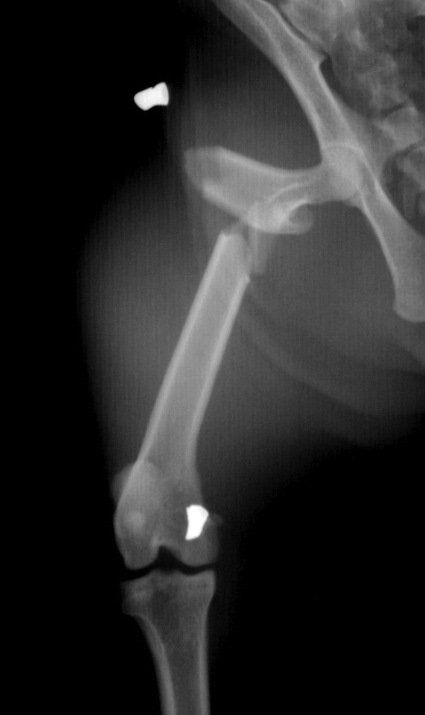

- Les traitements chirurgicaux dans la prise en charge de la dysplasie de la hanche images qui permettent d’améliorer le pronostic locomoteur du chien ainsi que sa qualité de vie.

- Les chirurgies réparatrices lors de fractures des membres avec utilisation de broches, plaques et vis.